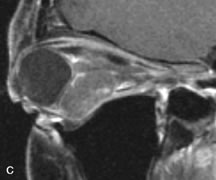

Tl relaxation time is the time required for the energized nuclei to give up the excess energy that was acquired from the RF pulse (high-energy state) and re-establish equilibrium (low-energy state) with the main magnetic field. The excess energy is released by these excited nuclei to the surrounding molecular environment, or lattice, and results in T1 relaxation, also called spin-lattice relaxation time. In different biologic tissues, hydrogen has a Tl ranging from a few hundred milliseconds to a couple of seconds. This range exists because local tissue factors affect the ability of specific protons to give up energy to the surrounding tissues. For example, hydrogen atoms attached to the carbon atoms of fat molecules relax much more rapidly than those attached to the oxygen atoms of water molecules. Viscosity, concentration, temperature, and molecular environment of the hydrogen atoms in the tissues also affect the T1 relaxation time. On a T1-weighted orbital image, fat, which has a very short T1 relaxation time, yields a high-intensity signal; the rectus muscles, which have an intermediate T1, yield an intermediate-intensity signal; and the vitreous, which has a long T1, yields a low-intensity signal (Fig. 8).5,8,16

Application of a 90° RF pulse brings the excited nuclei into phase so that the net vector of their magnetic moments is directed perpendicular to the static magnetic field. Shortly thereafter, the magnetic moments of the nuclei spread out and point in different directions, leading to a loss of phase coherence and a resultant decay in signal intensity amplitude. The T2, or spin-spin relaxation time, is the rate of decrease in the signal of these excited nuclei as a result of the interaction and transfer of energy to unexcited adjacent nuclei. T2 ranges from a few milliseconds to a few hundred milliseconds and, for a given tissue, is always less than the Tl relaxation time. T2-weighted orbital images are easily recognized by a high-intensity signal from the vitreous (Fig. 9).5,8,16